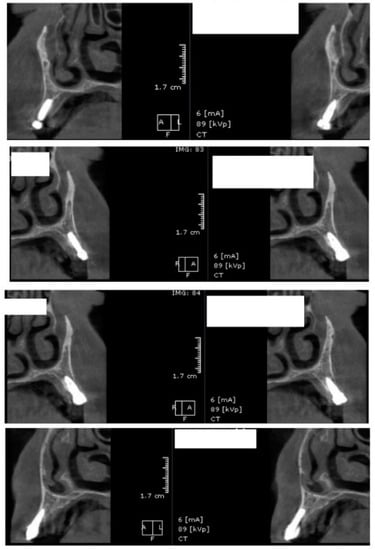

After 60 days of healing process, new CBCT images were recorded in order to assess bone density changes that might have occurred near the implant sites (Figure 9, Figure 10 and Figure 11).

Figure 9.

Random CBCT images with conventional healing caps in place.

Figure 10.

Random CBCT sections with pulse electromagnetic healing caps in position.

Figure 11.

Random CBCT images with pulse electromagnetic healing caps in position.

In the next phase of the study, after a healing period of 60 days, new measurements regarding bone density were recorded (Figure 12 and Figure 13). To avoid the metal artifact/beam hardening effect created by implants, new measurements were recorded at a 2 m distance from the implant site.